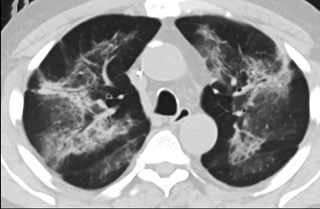

疑點(diǎn)二,中國(guó)科研工作者從60篇研究論文中篩選出142位電子煙肺炎患者的250張影像圖片,邀請(qǐng)3位放射科權(quán)威專家,對(duì)上述全部影像圖片、相關(guān)病人臨床信息以及文獻(xiàn)原文進(jìn)行了仔細(xì)全面研究與審查,又有了新的發(fā)現(xiàn)。

6天后的軸向CT平掃圖像顯示毛玻璃影變?yōu)閷?shí)變和輕度結(jié)構(gòu)扭曲。(同一病人CT影像)